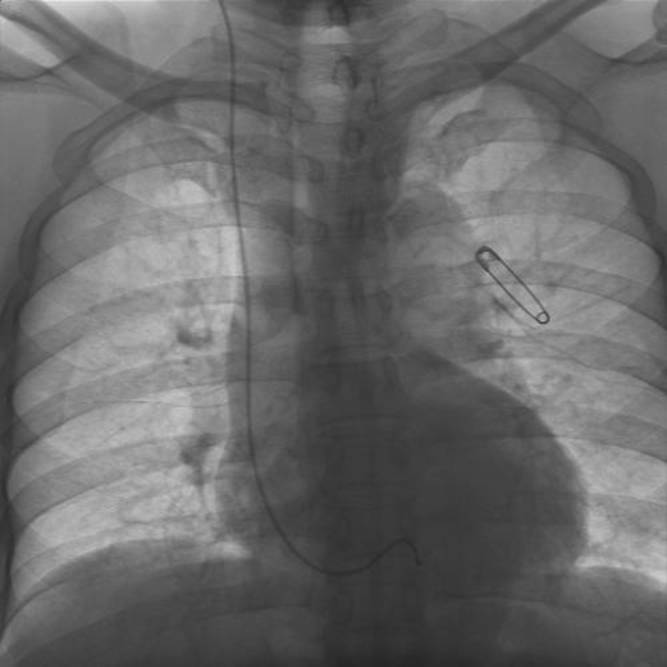

PM除去⇒体外ペーシング(感染の有無検査で1週間寝たきり)

さて今日は除去、そして体外式ペーシングの取り付け、二度目である。只今回は除去後の経過を見るためである。

手書きでメモしておいた内容をパソコンで整理する。今、ベッドの上は配線だらけだ。ちょっと油断すると絡まりあってしまう。

手術用の体外式ペーシング(MEDTRONIC5375

DEMAND PULSE GENERATOR) が、35 PPMに設定されている。

自己脈はほぼ42前後で安定している。この配線が右頚から静脈を経て心臓に当てられている。

それと、テレメトリー式心電送信機(心電・呼吸送信機)の三本線が、身体に貼り付けられている。ナースセンターで四六時中監視しているのだ。まぁ、ペースメーカー植え込んだ時点で自分もコンピュータ化されてしまった。

201201261234